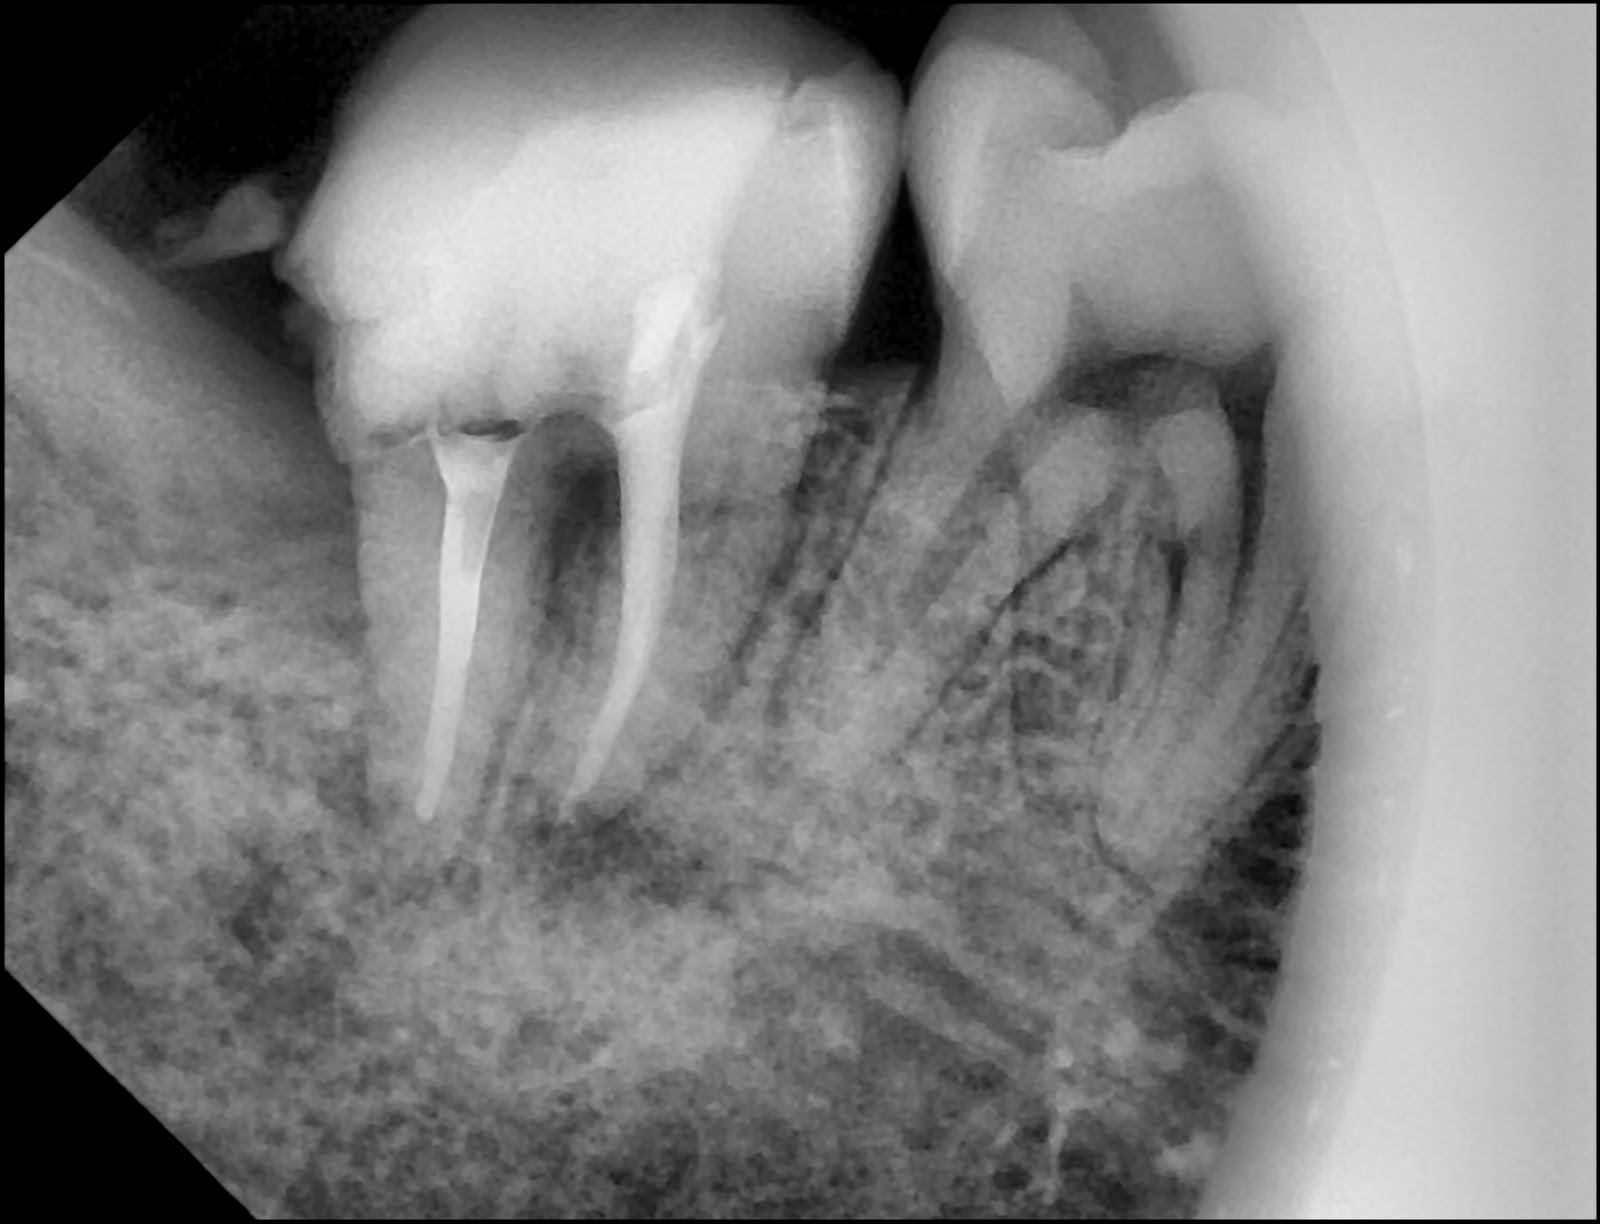

모니터의 파노라마 사진을 보니, A 위치(#37)에 뿌리까지 심하게 썩은 어금니가 보인다.

사랑니 때문에 옆 어금니에 심한 충치가 생김

눈으로 볼 때보다 훨씬 깊은 곳까지 충치가 진행중이다.

뒤쪽의 사랑니로 인한 뿌리 충치임이 확실하다.